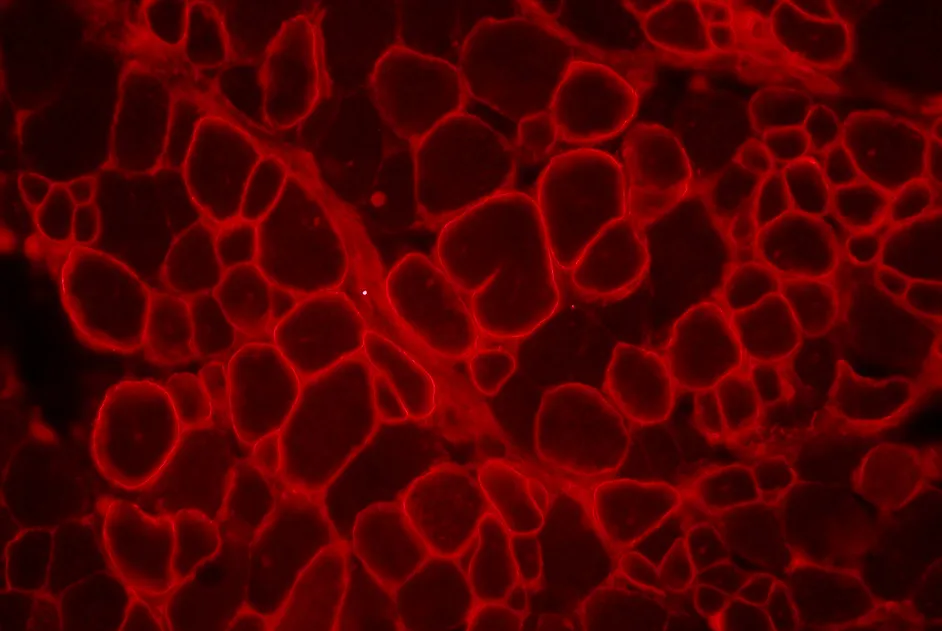

Une méthode pour obtenir des fibres musculaires et des cellules souches satellites à partir de cellules souches embryonnaires et iPS vient d’être publiée dans Nature Biotechnology (édition print du 8 septembre 2015).

Une méthode pour obtenir des fibres musculaires et des cellules souches satellites à partir de cellules souches embryonnaires a été mise au point par une équipe soutenue par l’AFM-Téléthon.